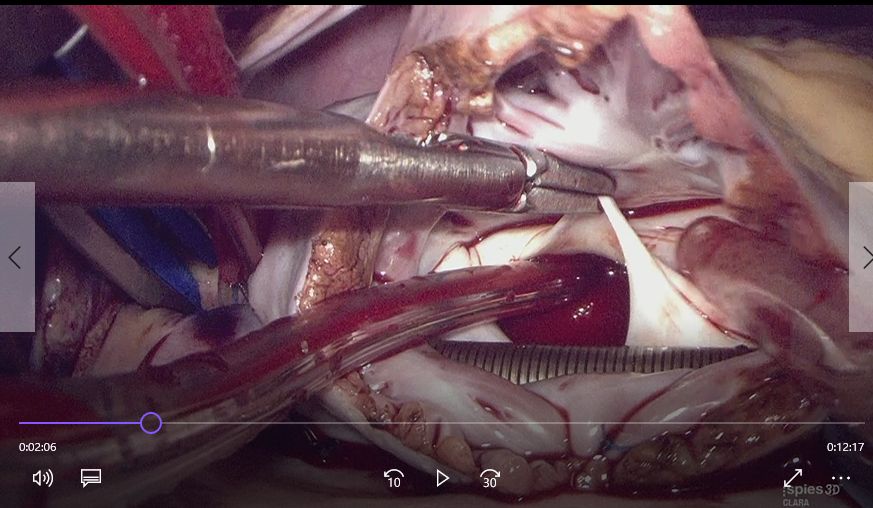

この度EMIファクトリー様より同等品の作成、販売が始まります。形状は同一ですが先端のブレード部分がステンレス丸棒の曲げ加工からNC加工機での切削に変わり、恐らくかなり早い納品が可能になります。サイズは左房こうが長中短の三種です。ほとんどは中で適正です。しかし体格が大きい場合長が必要になり、小柄な方や三尖弁展開には短が便利ですので3本全て揃えるのを推奨します。写真右の長く少し幅が狭いものは心膜横洞を展開して左心耳切除する為のものです。もう一本小型の大動脈弁展開その他ちょっとした展開に用いるものを加えると5本です。一見無駄に思えるかもしれませんが鏡視下手術はたった1本の道具があると無いとで全くやり易さや更に結果も違って来るものなので、多分揃えて無駄にはなりません。早い納品が必要な場合はEMIファクトリー様に注文をお願いします。